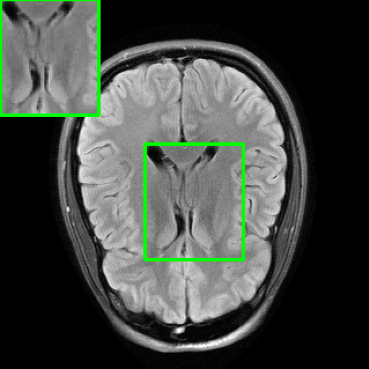

In Table 2, we replicate the experiment conducted in Table 1, this time utilizing the brain dataset. Notably, MoDL underwent fine-tuning using perturbed purified examples sourced from the training set of the brain data.

When comparing the results of our proposed method with other robustification approaches, we find that similar observations remain consistent. An important point to highlight is that the pre-trained DM employed in our purification stage for this experiment was originally trained exclusively on knee data, without any exposure to brain data. This underscores the robust generalization capabilities of the diffusion purification process within our approach, extending its effectiveness to previously unseen MRI datasets.

It’s worth mentioning that similar diffusion model generalization capabilities were also observed in the study conducted by Chung et al. [20]. However, further thorough investigation is required to precisely determine the limitations of these generalization capabilities, and this remains a promising direction for future research.

5.4 Visualizations

We now present visual samples from both the knee and brain datasets. Specifically, Figure 5 presents visual comparison of image reconstructions and their associated reconstruction errors within a closely examined region. Each image in the figure includes two inset panels in the top-left and top-right corners. The top-left inset panel, enclosed within a green bounding box, serves as a reference for the region of interest in the image. In contrast, the top-right inset panel depicts an error map in relation to the ground truth. Notably, our method stands out in its ability to capture the original image’s features, surpassing the performance of alternative methods (as also evident from the reported PSNR values). This visual comparison underscores the superior quality and accuracy of our approach in the robustification of the MRI image reconstruction task.